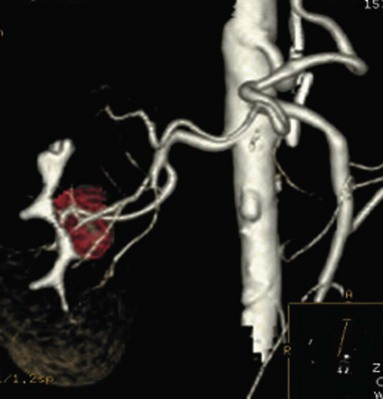

Before partial nephrectomy, evaluation of patients with renal cortical tumors should include imaging to identify locally extensive or metastatic disease. Preoperative imaging should also delineate relevant regional anatomy, intrarenal anatomy, and vasculature to minimize blood loss and damage to adjacent renal parenchyma. Invasive renal arteriography has largely been replaced by noninvasive 3D CT angiography, which offers excellent anatomic detail. 3D CT integrates information from arteriography, venography, excretory urography, and conventional two-dimensional CT into a single imaging modality (Fig. 54–130). In addition to tumor staging, 3D reconstructions of contrast-enhanced CT angiograms, MR images, or MR venograms are useful for planning site and extent of planned resection and to determine proximity to the renal hilum, intrarenal vasculature, and collecting system (Fig. 54–131). 3D CT accurately demonstrates involvement of the collecting system by tumor (Derweesh et al, 2003).

Figure 54–131 A, Contrast-enhanced CT scan demonstrating right renal mass. B, Three-dimensional reconstruction demonstrates a large intrarenal component to the mass. C, Arterial reconstruction shows lower pole renal artery in close proximity to the renal mass.